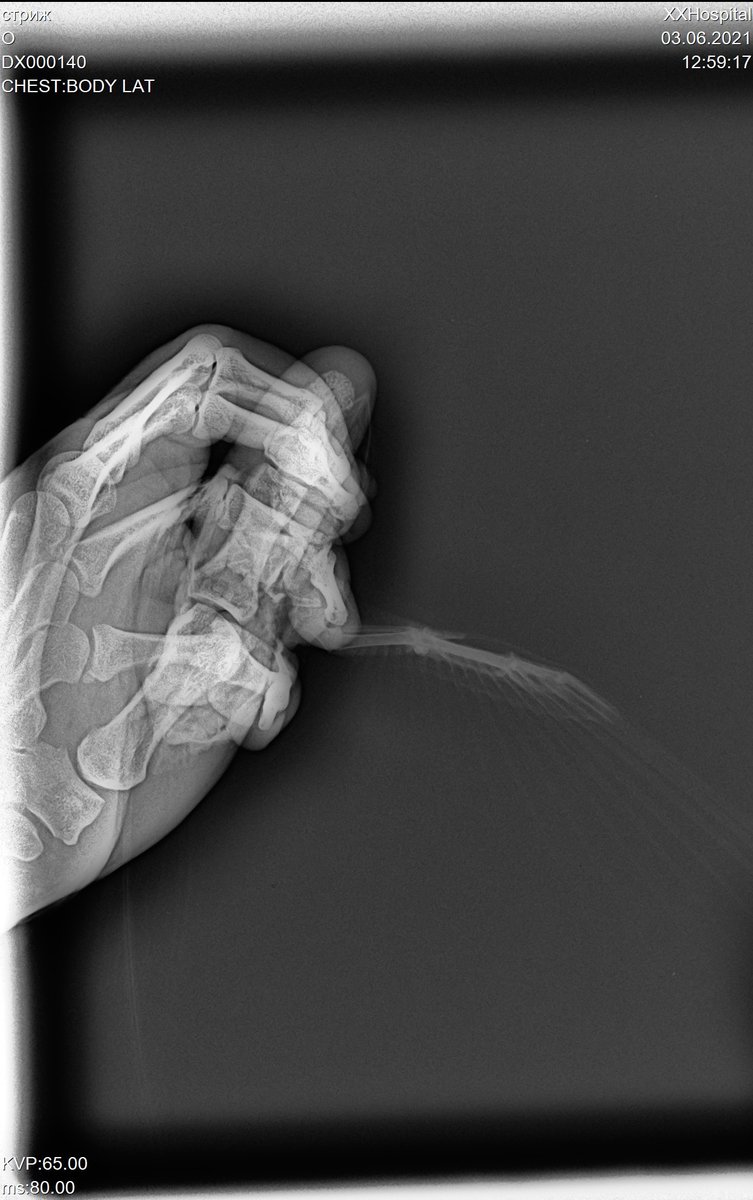

сделали ренген стрижу, только специалистов по птицам в клинике нет.. хотя бы знать нет ли  ничего серьезного.. ехать в москву нет возможности.

DX000140_1.jpg

@валена простите, не видела раньше вашу тему. Что-то с оповещениями не то. К сожалению, по данному рентгену можно очень мало чего сказать. Он совершенно бездарен.

Разве что если переделать? Стрижа для снимка кладут на спинку и полностью  раскрывают его крылышки. Нужен только 1 снимок.